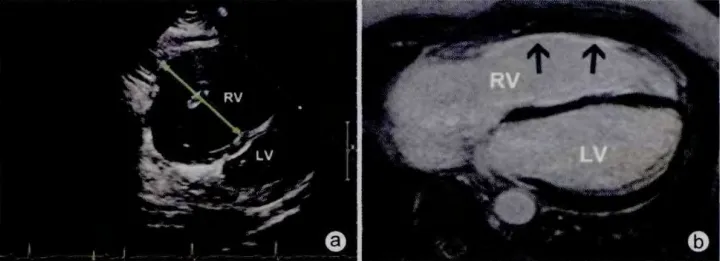

致心律失常性心肌病(图 6 )特点为脂肪和纤维替代心肌细胞而引起心室结构和功能异常,临床多累及右心室,也可双心室受累,患者多伴有心律失常。

右室扩大、右室壁变薄、右室壁运动异常、室壁瘤形成以及右心功能障碍是致心律失常性右室心肌病的典型超声心动图改变。

超声心动图对致心律失常性心肌病诊断的敏感性、特异性都不高。CT 和 MRI 具有较高的分辨率,是目前理想的无创性检查手段,可以显示心肌脂肪浸肌小梁稀薄化以及右室室壁齿状表现等特征性改变。

图 6 超声示右室明显增大,右室游离壁变薄, MRI 示右室游离壁变薄,心肌纤维化(箭头)